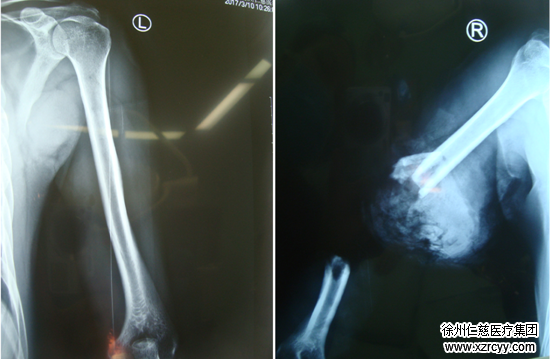

3月10日,徐州仁慈医院又完成一例大肢体离断再植手术,目前患者已出院,其离断的右上肢成功“复活”。

术前检查

黎医生介绍“探查发现患者右上臂中段完全离断、磋商比较严重,肱骨粉碎性骨折、骨片游离,肱动脉及伴行静脉、头静脉残端挫伤。同时,由于创口遭受到了挤压,断端血管、神经碾挫较重,情况非常严重,需要立即实施清创和断肢再植”。